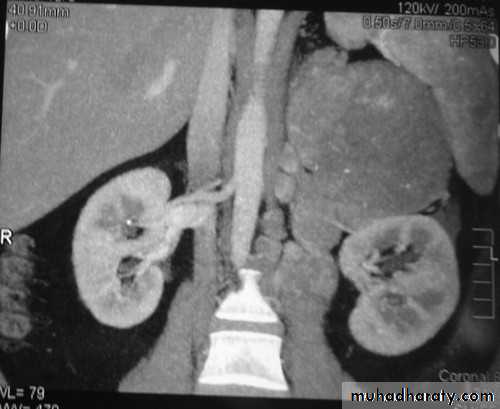

• Phaeochromocytomas are usually large tumors, measuring up to 12 cm with an average around 5 cm.

• CT of the abdomen, with particular attention to the adrenal glands is the initial imaging investigation of choice in the diagnosis of phaeochromocytoma.

• When the adrenal glands are normal on CT and no obvious mass is seen elsewhere, whole body scintigraphy with iodine labelled metaiodobenzylguanidine (131I-/123I-MIBG) may be useful.

• CT features of adrenal carcinoma/metastasis include:

• Relatively large size (>5 cm)

• Higher density on unenhanced scans with low density centrally due to necrosis

• Other evidence of malignancy, such as liver metastases, lymphadenopathy, venous invasion.